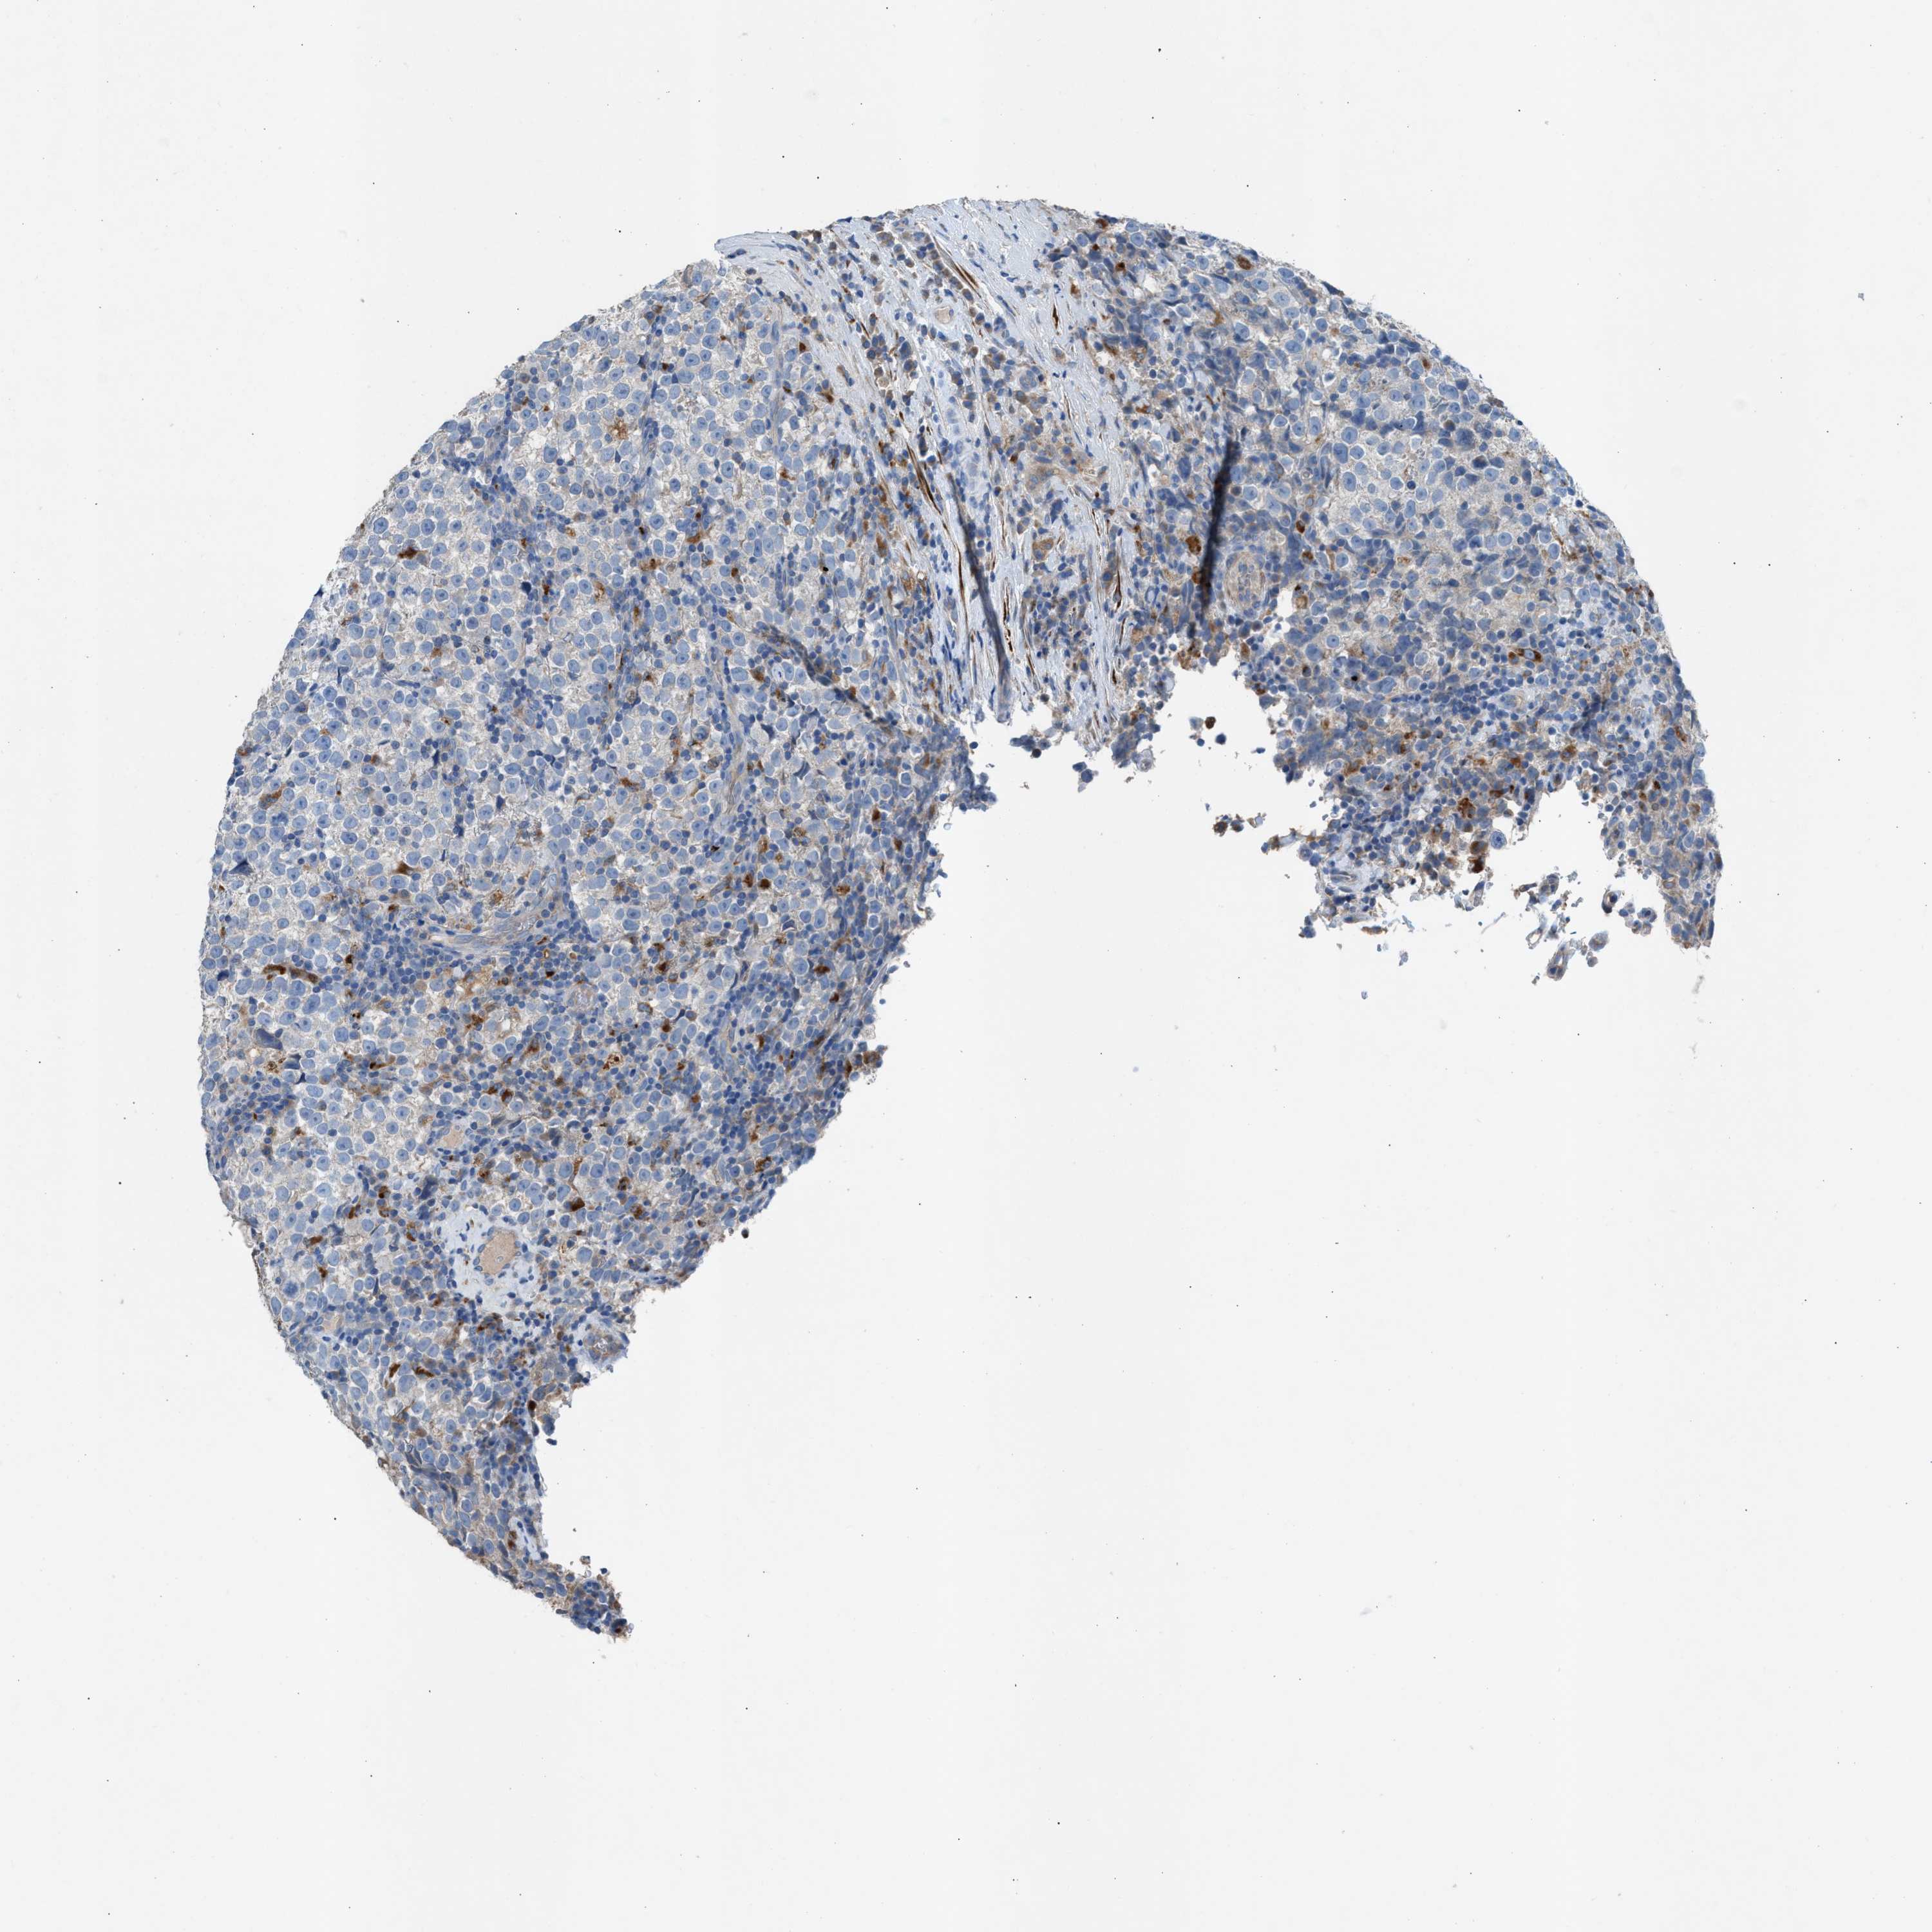

TESTIS CANCER - Protein expressioni

A mouse-over function shows sample information and annotation data. Click on an image to view it in a full screen mode. Samples can be filtered based on level of antibody staining by selecting one or several of the following categories: high, medium, low and not detected. The assay and annotation is described here.

Note that samples used for immunohistochemistry by the Human Protein Atlas do not correspond to samples in the TCGA dataset.

Antibody stainingi

Antibody staining in the annotated cell types in the current human tissue is reported as not detected, low, medium, or high, based on conventional immunohistochemistry profiling in selected tissues. This score is based on the combination of the staining intensity and fraction of stained cells.

Each image is clickable and will lead to virtual microscopy that enables deeper exploration of all samples and also displays staining intensity scores, fraction scores and subcellular localization as well as patient and tissue information for each sample.

Antibody HPA021666

Antibody HPA026716

Staining

High

Medium

Low

Not detected

Intensity

Strong

Moderate

Weak

Negative

Quantity

>75%

75%-25%

<25%

None

Location

Nuclear

Cytoplasmic/membranous

Cytoplasmic/membranous,nuclear

Carcinoma, Embryonal, NOS

Seminoma, NOS